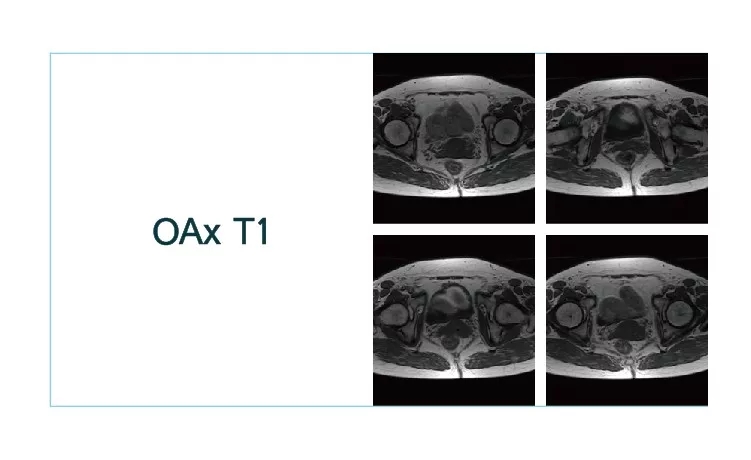

【朗润影像档案】20180930磁共振影像病例结果讨论